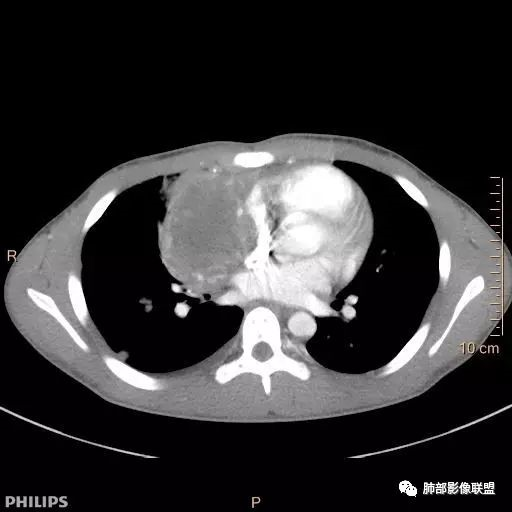

一切∮随缘: 前纵隔偏右侧实性占位,向右肺挤压,右肺膨胀不全,右侧胸水,心包似乎也有胸水,病灶较大无增强,平扫密度欠均匀,内部似可见低密度坏死及高密度钙化影,年轻男性,考虑恶性,生殖细胞肿瘤(精原细胞瘤?恶性畸胎瘤?),鉴别神经母细胞瘤,肺母细胞瘤,PNET?

秦化君: 右前上纵隔软组织密度肿块,边缘部分清晰澎隆,与血管及心包间界线不清,密度较均匀。挤压相邻肺组织形成膨胀不良,侵及胸膜形成胸腔积液。双肺内见随机分布结节。考虑纵隔恶性占位(肺及胸膜转移),生殖细胞瘤,畸胎瘤,淋巴瘤。建议穿刺活检。

放射线 (王秀仙): 右侧前纵膈巨大肿块,与纵膈大血管分界不清并受压,右肺组织受压膨胀不全,密度不均,内可见高密度钙化及低密度坏死区,双肺多发结节状转移灶,右侧胸腔积液,年轻男性,考虑生殖细胞肿瘤,精原细胞瘤可能性大。

宇宙: 男性小孩,右前纵膈不规则肿块,与心脏及大血管分界不清,邻近肺组织受压,其内可见钙化及低密度坏死,两肺多发类圆形结节,右侧胸水,考虑精原细胞瘤伴两肺及胸膜转移,鉴别恶性畸胎瘤。

金豆 (刘权威): 病灶主体位于纵隔,密度不均,内可见点状钙化灶,邻近肺组织受限不张,两肺散在结节,右侧胸水,9岁,恶,生殖类,恶性畸胎瘤,鉴别精原。

放射小白: 男9岁,胸痛,定位右前纵隔占位,内部可见钙化灶,右肺局部实变,两肺散在结节灶,右侧胸腔少量积液,常规考虑生殖类肿瘤,精原细胞瘤伴两肺转移,请结合实验室检查。

良孑: 右侧前纵膈巨大肿块,与纵膈大血管分界不清并受压,右肺组织受压膨胀不全,密度不均,内可见高密度钙化及低密度坏死区,坏死边界不清,双肺多发结节状转移灶,右侧胸腔积液,定性恶性,考虑生殖细胞肿瘤,精原细胞瘤或内脏窦瘤可能性大。

位移: 右侧前纵膈巨大肿块,内可见钙化及坏死区,两肺多发结节状转移灶,右侧胸腔积液,儿童,男,考虑生殖细胞肿瘤,精原细胞瘤可能性大,其次恶性畸胎瘤,外周性原始神经外胚层肿瘤。

蔡磊: 男孩,9岁,胸痛10天就诊。前纵隔偏右侧巨大肿块,内见点状钙化,与周围大血管结构不清,推移挤压。右肺受压,节段性不张。增强后双肺内多发类圆形实性结节。恶性病变肺内转移,生殖可能。

右前纵隔巨大软组织肿块,主要偏向右侧生长,边界不清,密度不均匀,内见大片状低密度坏死区及散在钙化灶,未见骨骼影及脂肪密度影。、双肺随机分布的转移瘤结节,右肺肺不张及右侧胸腔积液,提示恶性肿瘤病变伴双肺及胸膜转移。